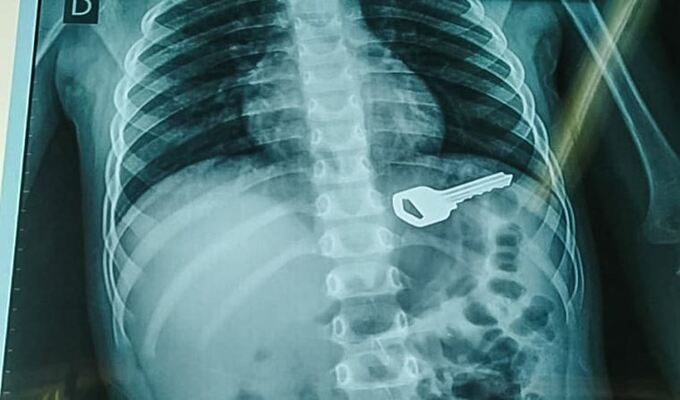

Asimismo, en Huánuco, recientemente los profesionales de la salud pudieron salvarle la vida a un pequeño de tan solo cuatro años, tras intervenirlo quirúrgicamente para sacarle una llave de cinco centímetros.

Sobre este caso y cómo llegó el cuerpo extraño al organismo del menor, la doctora Edith Altamirano, contó que el menor estaba jugando en su vivienda cuando ingirió el objeto.